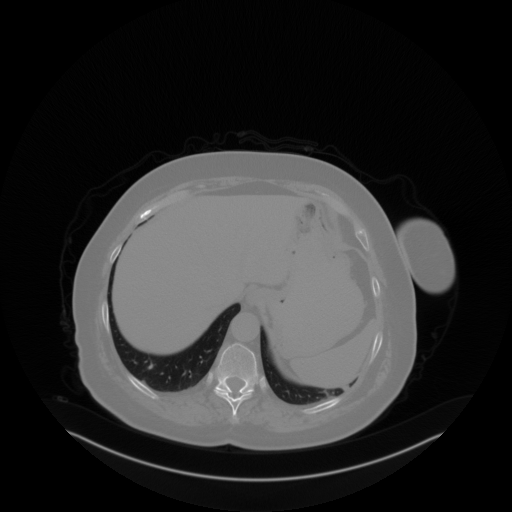

Reconstructed NATIVE CT scan (cycle consistency)

No window - Raw intensity values

Lung window (WL -600, WW 1500 β†’ Low βˆ’1350, High +150)

Mediastinum window (WL 40, WW 400 β†’ Low βˆ’160, High +240)